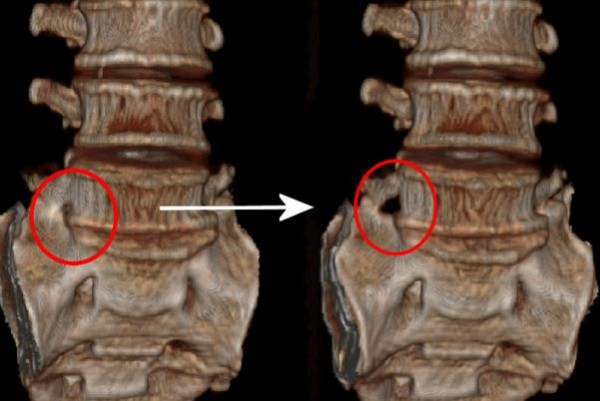

김순임씨는 좋은아침병원 척추센터에서 극외측 협착증으로 확진을 받고 미세도관 감압술로 수술을 받았다. 미세도관 감압술은 직경 18 mm의 가는 관을 수술부위에 삽입하고 그 도관을 통하여 미세감압수술을 현미경을 보면서 하는 수술로 전신마취나 수혈이 필요 없는 최소침습수술이다. 김순임씨는 수술 당일 통증이 사라져 정상적인 보행이 가능해져 매우 만족하였고 수술 다음날 퇴원하여 현재 정상적인 생활을 하고 있다.

(동그라미 친 부분이 좁아져 있던 부위를 미세도관 감압술로 넓힌 부위이다)